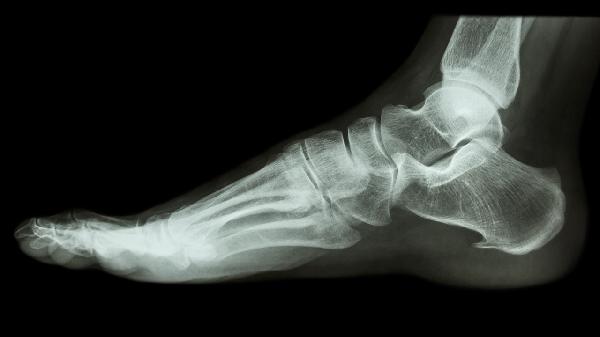

对于严重粉碎性骨折或关节面塌陷超过2毫米者,需行跟骨钢板内固定术或距下关节融合术。术后6周内禁止完全负重,定期复查X线观察骨折愈合情况。合并跟腱损伤者需同时进行跟腱修补术,术后采用长腿石膏固定。